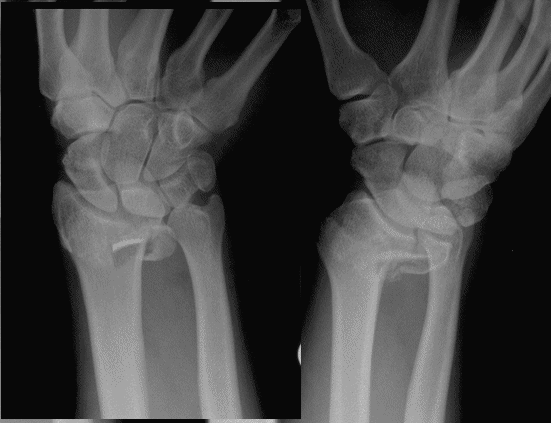

Case 4 Preop